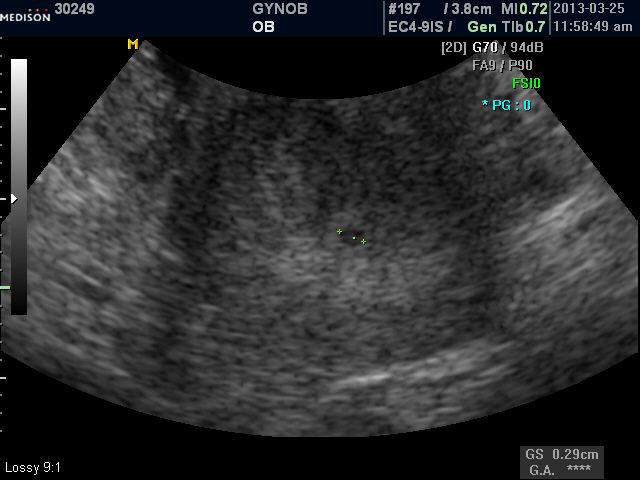

오늘 초음파를 보셨는데 두개의 아기집이 자리잡고 있네요..두 아기집 다 심장소리가 들려서 너무 벅찼어요.. 엄마는 아직 쌍둥이가  실감나지 않으신가 봐요..  건강하게 두 아기 다 잘 컸으면 좋겠어요~~^^

10# 김지연 등록시간 2013-04-05 12:56 |이 글쓴이 글만 보기

오늘 담당 간호사 분 한테  쌍둥이라는 말을 듣고 제가 오히려 기뻤습니다.